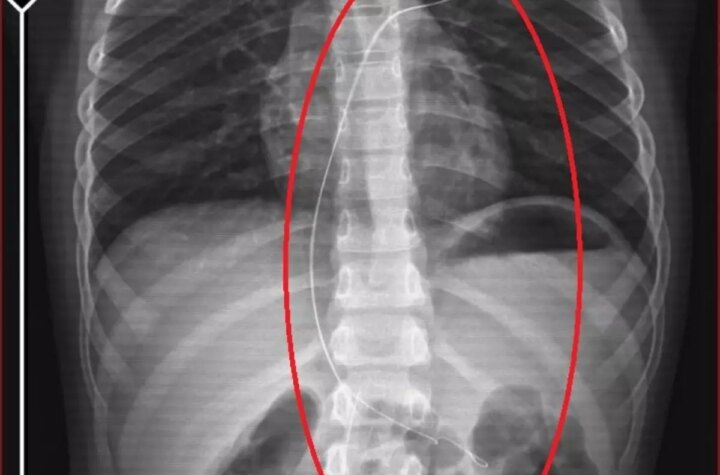

ŞIRNAK'ta piknikte salatalık kesimi yuttuktan sonra öksürük ve kusma şikayetleriyle hastaneye götürülen Aram Devran...